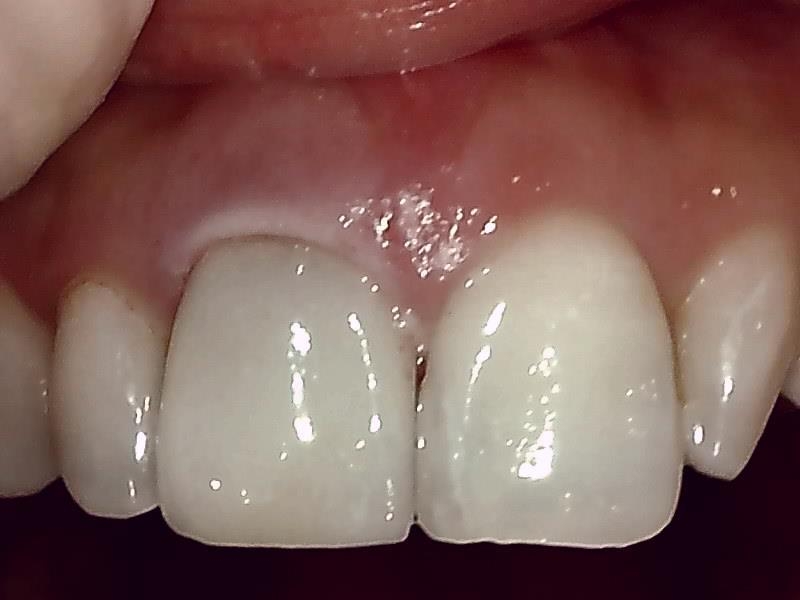

完成

治癒